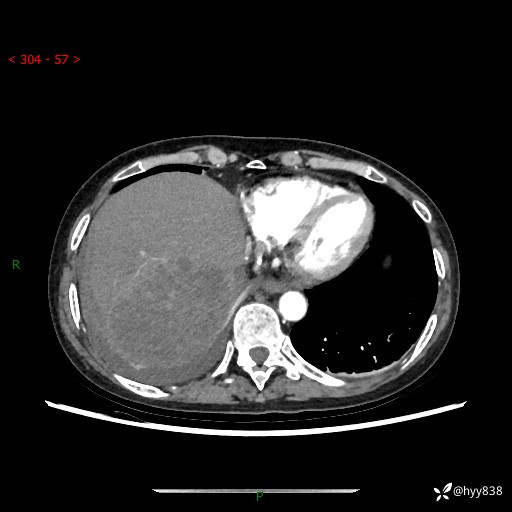

病例老年女性,发热来诊。如此“蜂窝煤”,治疗很棘手---结果公布~

性别:女

年龄:53岁

简要病史:发热(门诊急诊患者)

上腹部CT平扫